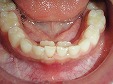

術後

乳歯の前歯が抜ける6、7歳の時期に上下前歯の歯並びがデコボコしてきた場合は、床矯正(取り外し可能な矯正装置)・食育・咀嚼訓練などを行い口腔周囲筋・咀嚼系筋群を活性させ正常な顎骨に発育させることで歯のデコボコを治していきます。床矯正を始める年齢・永久歯の萠出状態によりワイヤーによる歯列矯正も必要になる場合があります。